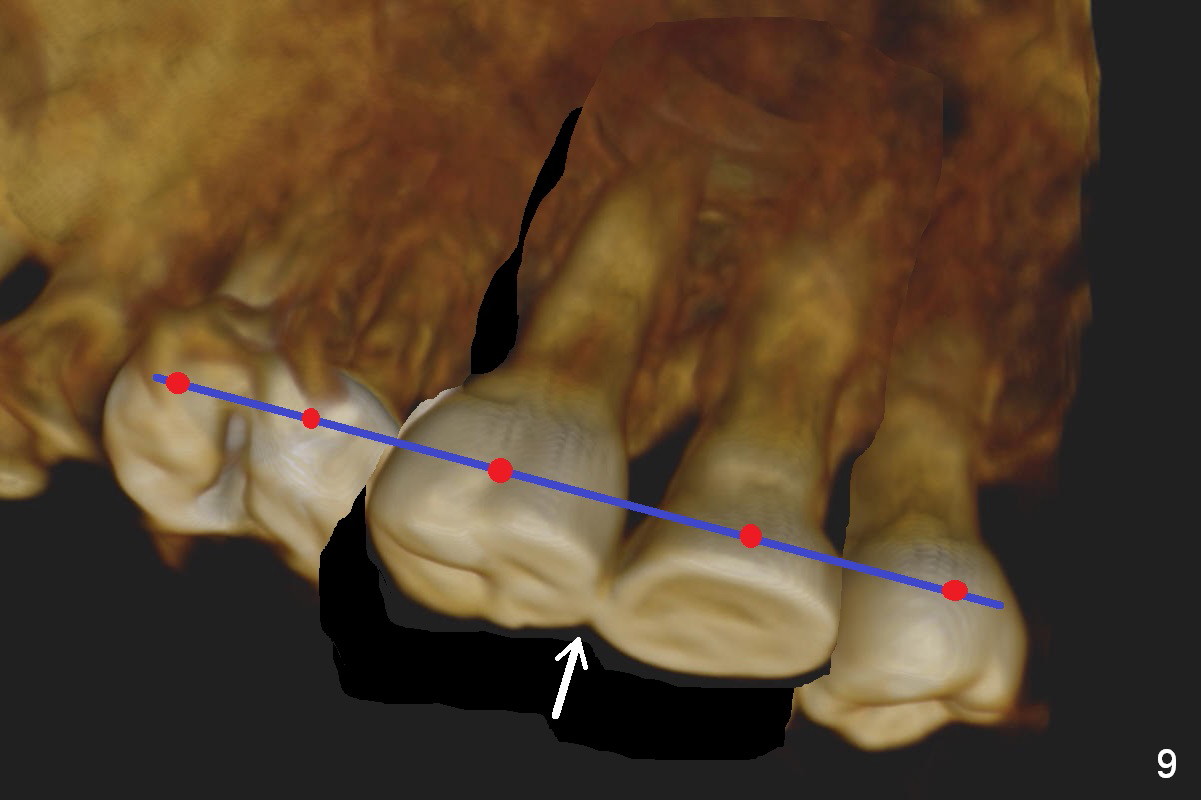

Orthodontic intrusion with mini-implants does not seem to work. When segmental brackets and bands are supplemented, the neighboring tooth (#14) becomes loose. CBCT 3 D and sagittal section show ~3 mm supraeruption of the teeth #2 and 3 (Fig.1,2). Diagnostic wax up demonstrates that the teeth #2 and 3 need to be intruded for 4 and 2 mm, respectively. Buccal gingival sulcus and anterior oblique incisions are shown in Fig.3 (red line). Osteotomy will be made with surgical fissure bur and chisels (Fig.4 red lines). The segment is down fractured (Fig.5 arrow). Apical bone is removed with acrylic bur and/surgical burs (Fig.6 cross lines). The segment is elevated and checked with a prefabricated splint out of diagnostic wax up. Insert a thicker orthodontic wire into brackets and bands buccally.